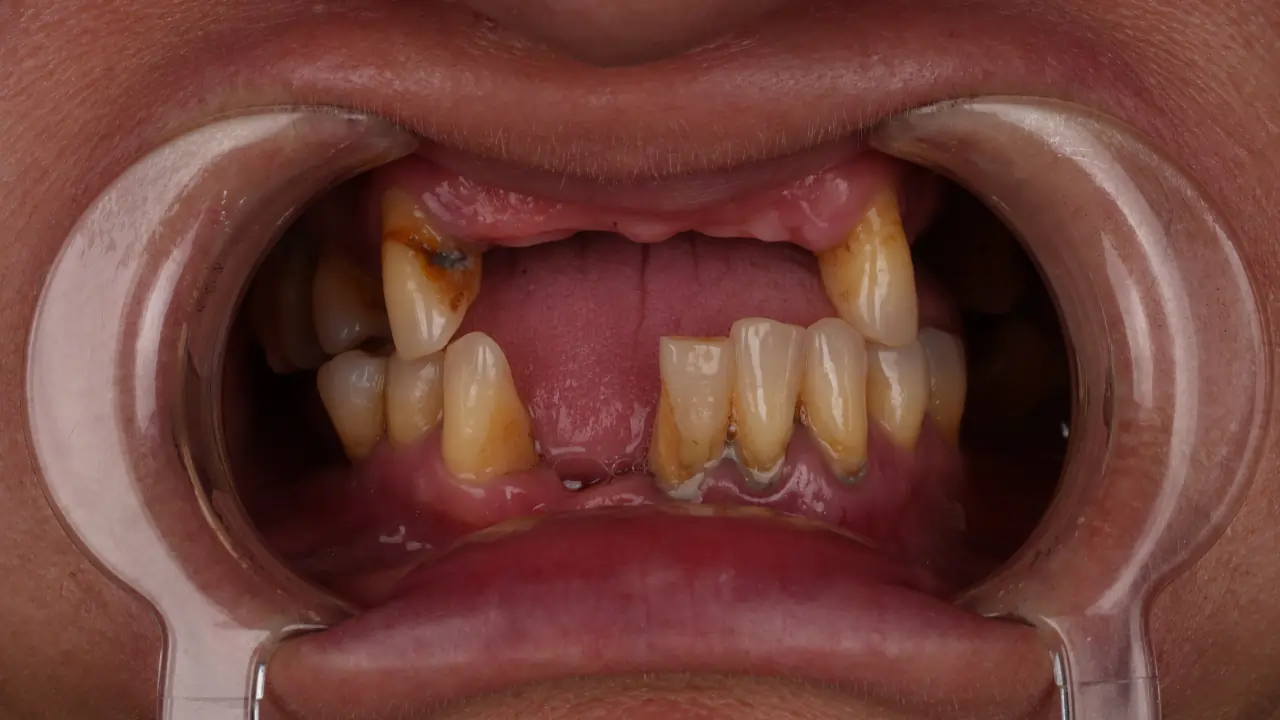

Metoda all on 6 Turcja jest szczególnie polecana osobom, które mają rozległe problemy z uzębieniem. Dotyczy to zarówno pacjentów całkowicie bezzębnych, jak i tych, u których zęby są w tak złym stanie, że ich odbudowa nie ma sensu. W wielu przypadkach jest to również najlepsza opcja dla osób noszących protezy ruchome, które chcą wreszcie odzyskać komfort życia.

Warto podkreślić, że implanty all on 6 są często jedynym rozwiązaniem, które pozwala uniknąć wieloetapowego i kosztownego leczenia pojedynczych zębów. Zamiast inwestować w kolejne zabiegi, które nie dają trwałego efektu, pacjent decyduje się na jednorazową, kompleksową zmianę.